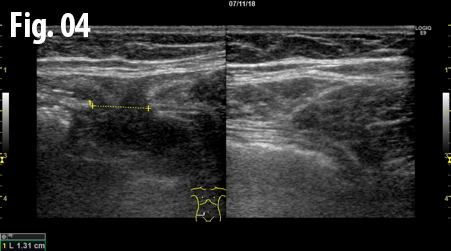

An ultrasound examination of the abdomen was performed using a GE Logiq E9 system with a linear array transducer and centre frequency of 9 MHz. The patient was examined in the supine and standing position including the Valsalva manoeuvre. The examination revealed an incarcerated hernia between the rectus abdominis and transversus abdominis muscles at the level of the anterior superior iliac spine. The dimension of hernial orifice was 1.3 x 0.7 cm and contained preperitoneal fat without any bowel loops. There was no change in size or content of the hernia on standing or Valsalva, and no signs of strangulation.

Figure 3 and 4: Comparison between right (left side) and left (right side) side, axial view obtained with the patient standing. The right and left rectus muscle (gray arrows) is located centrally in the image. The black arrow and marker indicate the hernia and the blue arrows indicate the transversus abdominis muscles. The yellow arrow indicates the intact fascia on the left side.